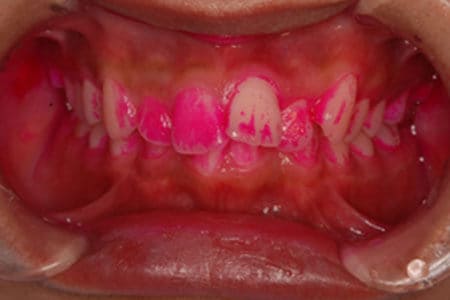

口腔内写真撮影

治療のステップごとに写真を撮影し、治療開始前と治療後の状態を比較することで客観的に治療の効果が比較できるようにしています。また、その他の検査データとともにより綿密な治療計画を立案するための参考としても使用します。